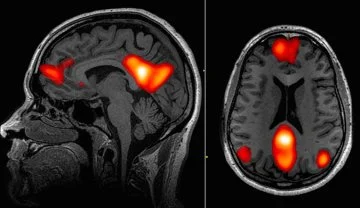

A study by researchers at Stanford University in July 2016 considered what takes place in the brain in general during hypnosis. Functional magnetic resonance imaging (fMRI) was used to observe brain activity in 57 subjects in hypnosis. Changes were observed in three specific areas of the brain:[11]

1. Reduced connectivity between the dorsolateral prefrontal cortex (part of the executive control network involved in planning and decision making) and the posterior cingulate cortex (the part of the default mode network that seems to be involved self-related thinking and one's sense of self). This may be responsible for the dissociation that can occur in hypnosis, enabling one to place certain events, thoughts, and sensations outside of the self and thus permit a shift in the cognitive set (i.e. belief system).

The inverse functional connectivity between regions involved in planning of actions and those involved in self-awareness may also account for the immediacy of action that takes place during hypnosis. In hypnosis, as in states of deep absorption in a task or performance, one acts spontaneously, without reflecting upon actions.

2. Increased connectivity between the dorsolateral prefrontal cortex (part of the executive control network involved in planning and decision making) and the insula (involved in sensing and regulating autonomic internal bodily processes). This may be why in hypnosis one has increased control over autonomic process (e.g.: pain perception, blood flow, temperature, dilation of the pupils).

3. Reduced activity in the dorsal anterior cingulate cortex (dACC). This is part of the salience network, which helps us to notice things that stand out to our attention (e.g.: when you see something out of place, hear a strange noise, or feel an odd sensation). The dACC is involved in the emotional evaluation of errors and worrying, and is active during effortful performance. Reduced activity in the dACC may explain the high level of focus that characterizes hypnosis, and why actions and performance take place effortlessly and with less worry in states of hypnosis and absorption (i.e. "flow").

Reduced activity in parts of the brain's default mode network (DMN) increases attentional absorption.

The DMN is a network of interacting brain regions that is active when a person is not involved in a task, and when thinking, remembering, and daydreaming. The DMN is not active when a person is involved in a goal-oriented task or has their attention completely absorbed by something.

Hypnosis reduces the activity of the DMN.[2] Reduced activation of the DMN is also observed in long-term practitioners of meditation. The fact that the brain under hypnosis shows reduced DMN activity supports the definition of hypnosis as a state of attentional absorption, rather than a state where one loses consciousness. Hypnosis shows neural responses similar to spontaneous conceptual thought. Perhaps this is why hypnosis can spark creativity and insight.

Increased activity in the prefrontal attentional systems increases executive function.

The frontal areas of the brain govern a person’s ability to concentrate, known as attentional control. Attentional control is closely related to executive functions such as reasoning, problem solving, planning, self-control, and cognitive flexibility (the ability to think about multiple concepts at the same time). Hypnosis increases the activity of the systems involved in these functions, and which are impaired in addiction and ADHD.[2]